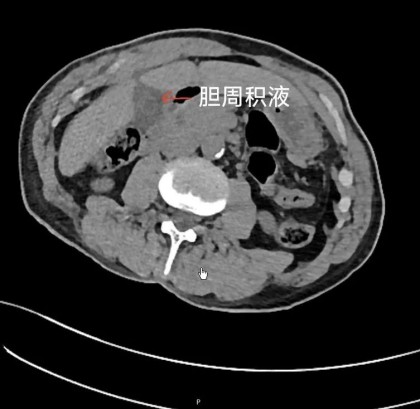

上腹部增强CT▼

肝胆外科朱涛主治医师接诊后查体,见患者有全腹压痛、反跳痛、腹肌紧张,考虑存在全腹膜炎,立即完善上腹部增强CT,提示:胆囊结石、胆囊穿孔。病情危重,极易发生感染性休克,危及生命!朱涛主治医师立即向患者及家属讲明病情,急诊行腹腔镜下胆囊切除术,术中见胆囊壁炎性水肿,胆囊底可见穿孔,大量胆汁流入腹腔,切除胆囊后反复清洗腹腔,经术后积极抗感染及营养支持治疗,患者于第二天即可正常下床活动。